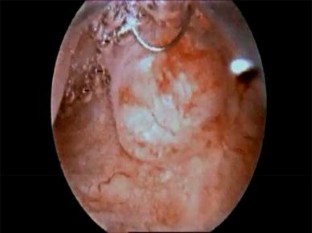

Fig. 3